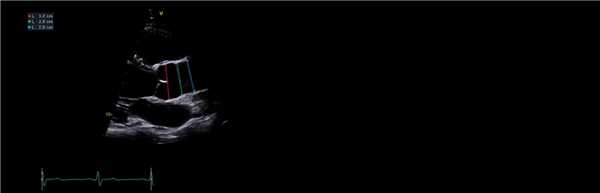

Размеры аорты следует измерять с помощью 2D-изображения из окна PLAX.

Индексы должны быть получены с использованием методологии от внутреннего края к внутреннему краю (IE-IE) в конечной диастоле, определяемой как начало комплекса QRS.

Измерения следует проводить на трех уровнях, включая: синус Вальсальвы (красная линия); синотрубчатый переход (зеленая линия); проксимальная восходящая аорта определяется как область на 1 см выше синотубулярного соединения (синяя линия).